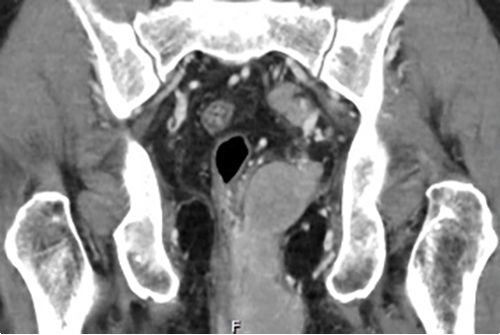

A positron emission tomography-computed tomography (PET-CT) scan was performed, demonstrating the left perianal mass predominantly occupying the ischiorectal fossa with a loss of the normal fat plane between the seminal vesicles and the rectal wall, suggesting local invasion (Figure 3). PET-CT was also significant for multiple enlarged pelvic and inguinal lymph nodes bilaterally, multiple hypermetabolic nodal stations below the diaphragm, and areas of extra nodal disease in the bone marrow and spleen, consistent with Ann Arbor stage IV disease.

Figure 3: CT I mages of Perianal Mass. Published With Permission

Hyperdense mass in left ischiorectal fossa, extending into left supralevator space

Left external iliac lymphadenopathy. Cranial extent of tumor with mass effect on rectum